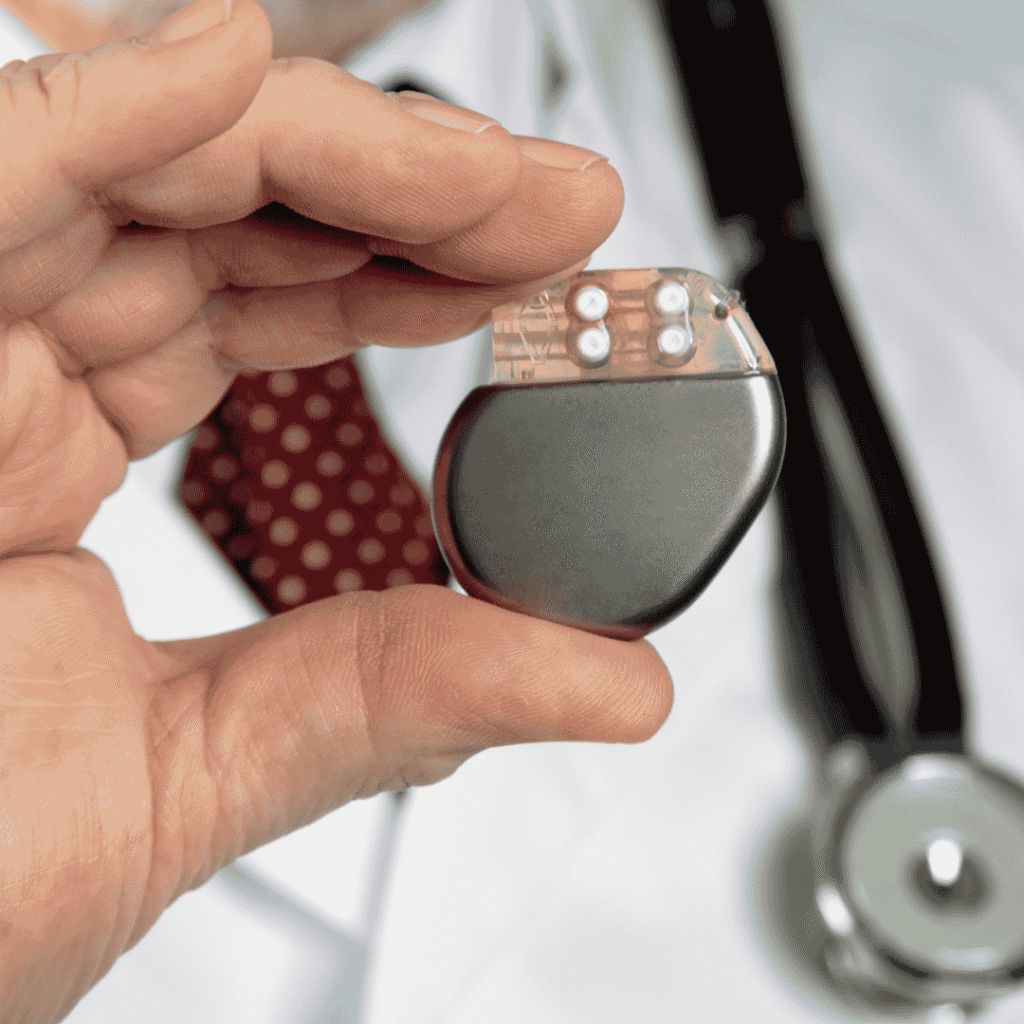

Device Selection

Choosing the right type of pacemaker based on individual needs and medical conditions, including single-chamber, dual-chamber, or biventricular pacemakers.